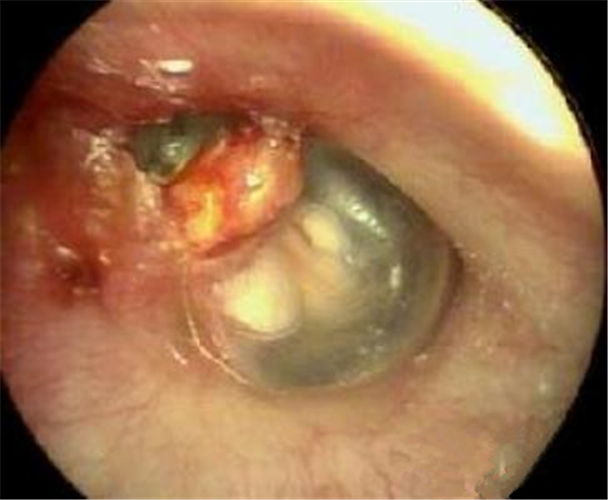

鼓膜穿孔圖片

左耳鼓膜穿孔

中耳炎鼓膜穿孔

中耳炎使鼓膜穿孔

炎症導致鼓膜穿孔

炎症導致的鼓膜穿孔